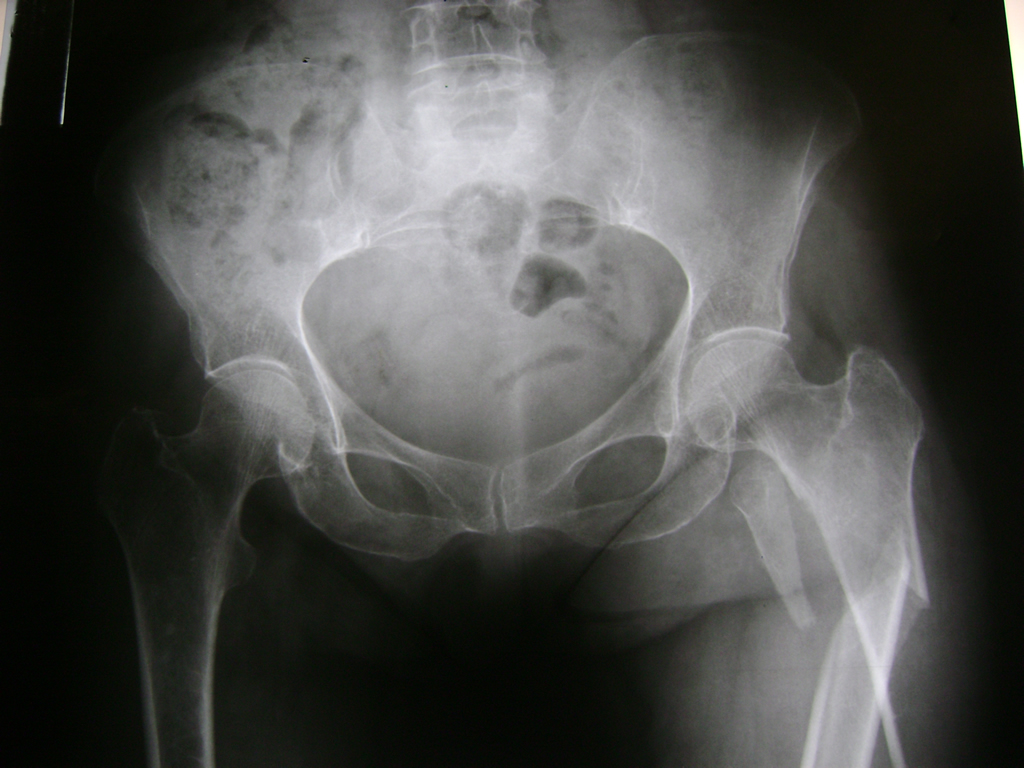

Cirugía de Fémur - Cadera

La cirugía de fractura de cadera se realiza para reparar una ruptura en la parte superior del hueso del muslo. Este hueso se denomina fémur.

Es parte de la articulación coxofemoral. Si una fractura de cadera no recibe tratamiento, es posible que deba permanecer en una silla o en la cama.